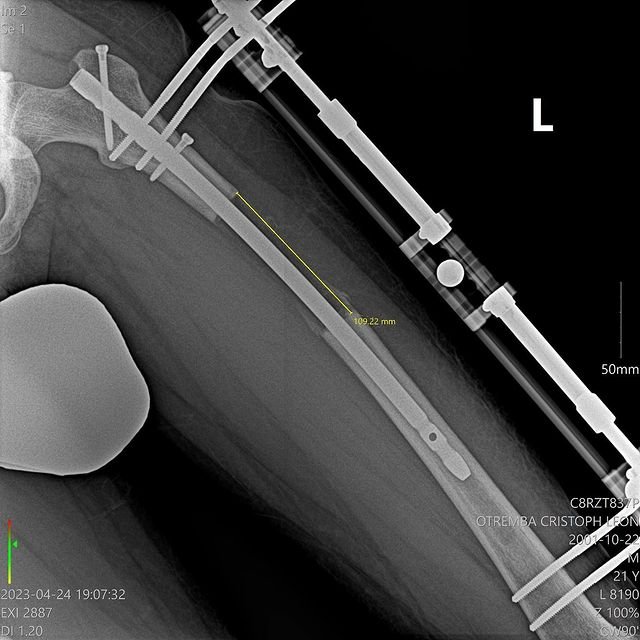

@le_tremba表示,因為他的原生身高只有172.5公分,讓他覺得自己偏矮、時常感到自卑,「老實說,170公分算滿矮的,這影響了我的自信心,我總覺得這樣不夠Man,因為就連有些女生都長到175公分甚至更高了。」因此他一心想要解決這個困擾他已久的身高問題,後來他特地飛到土耳其進行增高手術,前後共手術了3次,讓他的身高增加了10.5公分、來到183公分!

不過增高手術也不是那麼容易的,必須使腿部骨骼斷裂、並打入增長骨釘促進骨骼延長,不但程序繁複,接受手術者也必須承受很大的風險以及可能會發生的併發症,而且也不是做完手術就立刻長高,還需要一段恢復期來讓骨頭、肌肉、皮膚和神經慢慢伸展開來,過程當然也是必須忍受這非比尋常的「生長痛」;但@le_tremba堅信這個決定是正確的,他甘之如飴。